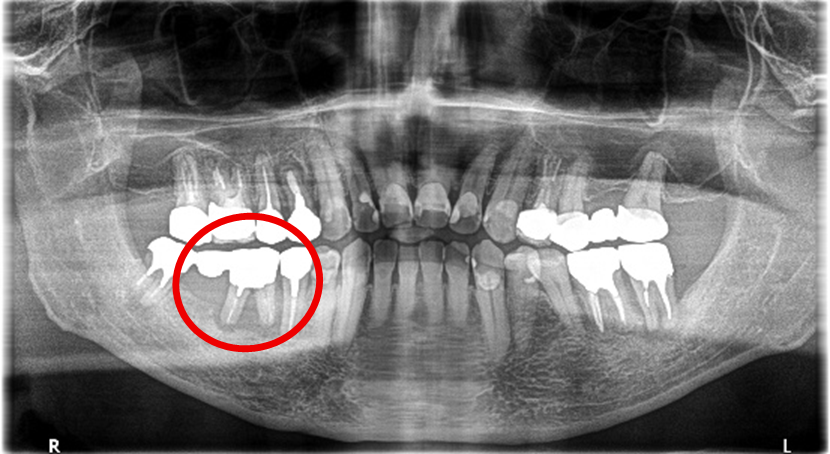

右下奥の歯が、グラグラして噛むと痛い。

治療内容

歯根の周りの骨が全く無い状態でしたので、保存することができず抜歯しました。3本歯がないところに2本インプラントを埋入しました。

Before

※赤丸を抜歯しました。

After